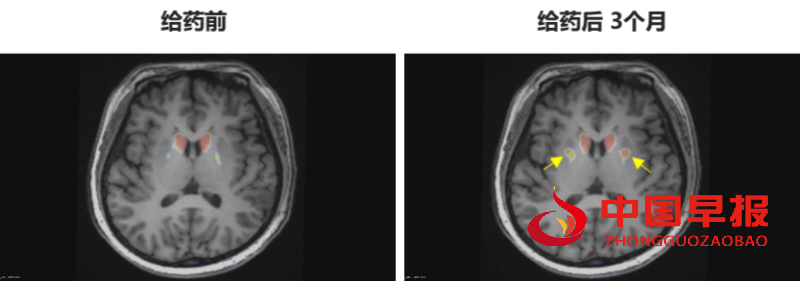

多巴胺能功能成像:神经突触多巴胺能显像是评估人脑黑质纹状体神经元完整性和功能的“金标准”,常用于帕金森病亚临床诊断1-2。接受移植手术3个月后PET-DAT/MRI融合影像明确显示,移植细胞已在患者脑内定植并成功转化为有功能的多巴胺能神经元,双侧纹状体形成显著的de novo新生多巴胺能活性成像(如下图箭头所指), 为功能性治愈提供了最直观的证据。

EOPD患者PET-DAT/MRI融合图像术前与术后三个月对比

注:影像图中黄色箭头指示为NCR201移植后,双侧纹状体出现的新生多巴胺能活性信号,提示移植细胞已定植并高效转化为功能性多巴胺能神经元